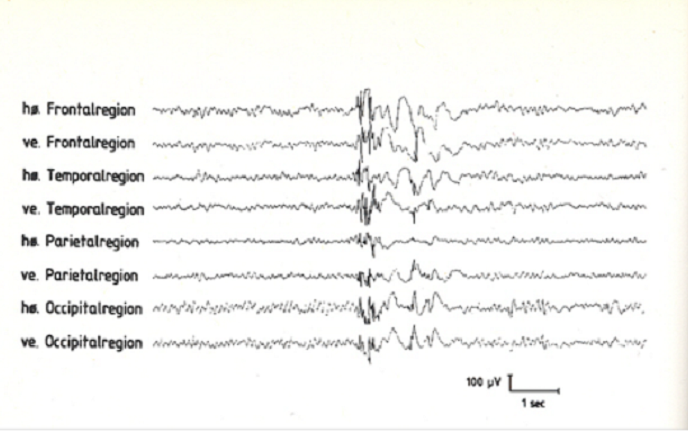

17-årig pige kommer til konsultation i epilepsiklinikken. For 14 dage siden havde hun et generaliseret krampeanfald om morgenen, efter at hun havde været i byen aftenen forinden og havde drukket 5 øl. Hun oplyser nu, at hun de sidste 6 mdr. har haft tendens til at få ukontrollerede spjæt i armene om morgenen, så hun flere gange har tabt ting. Hun er i øvrigt rask og klarer sig godt i skolen, men føler sig stresset af skolearbejde og fritidsjob.

Der foreligger nu eeg.

Hvilken diagnose vil du stille?

e. Juvenil myoklon epilepsi